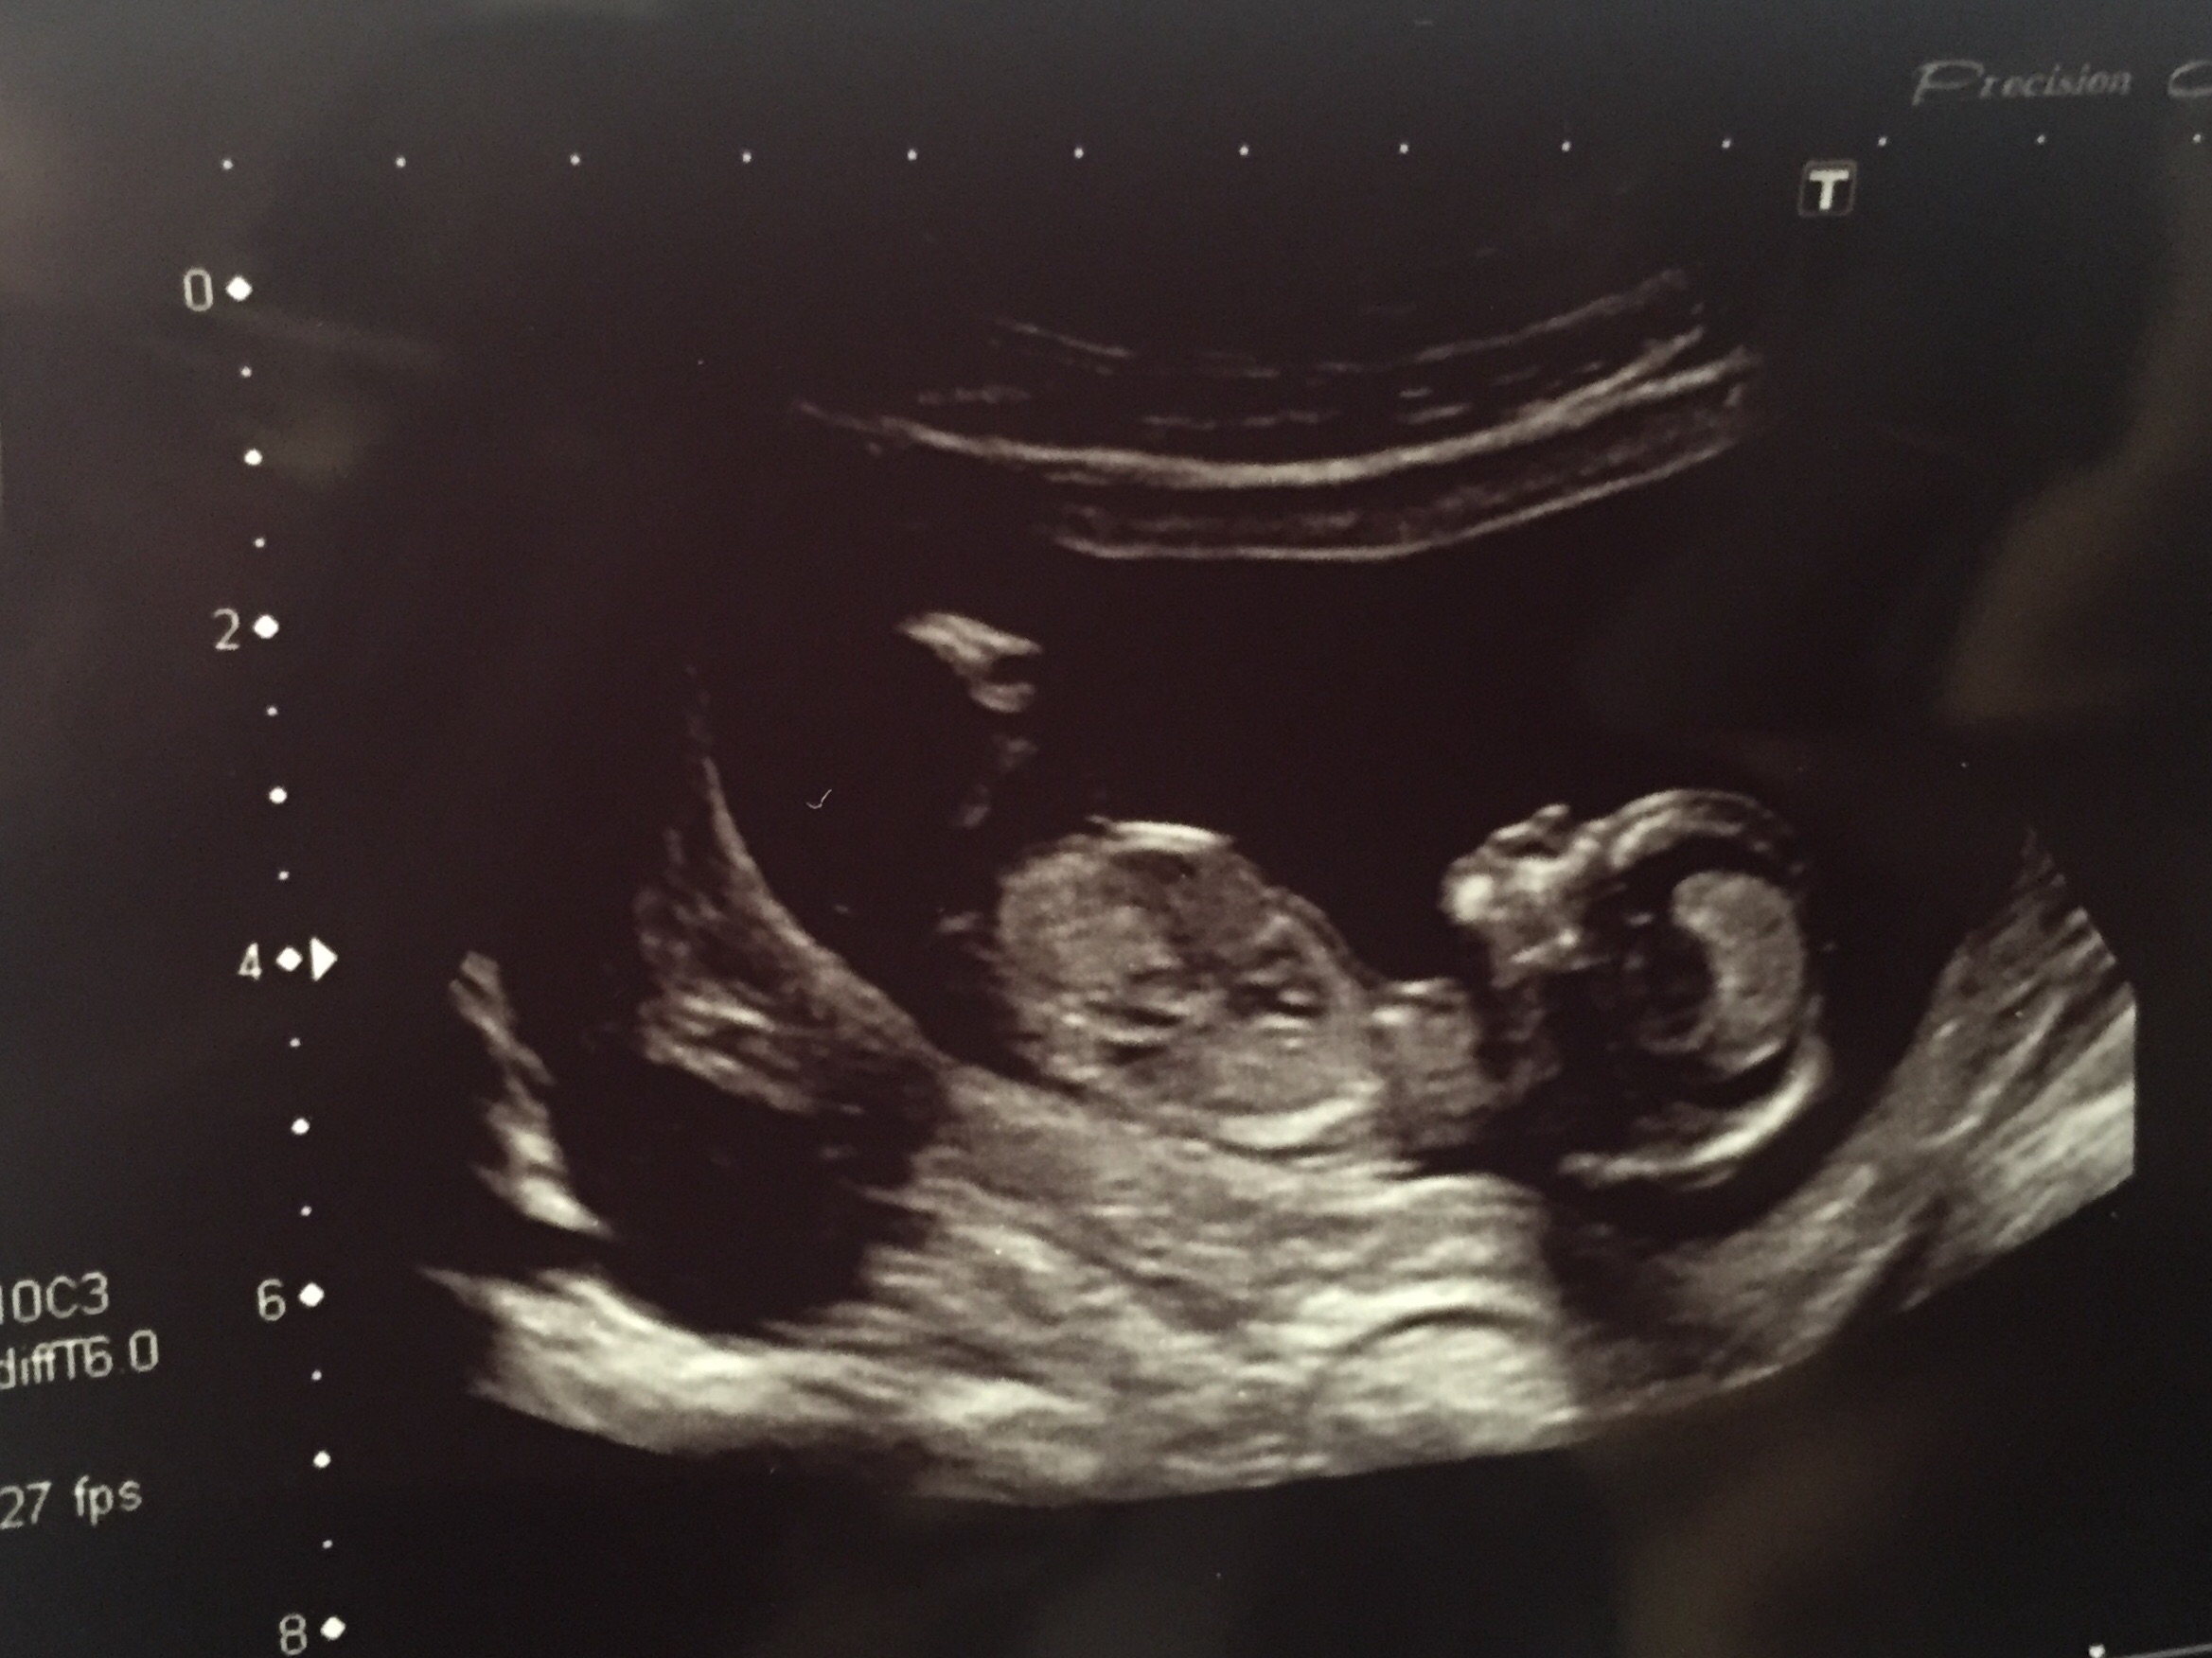

Gender predictions please!

Boy or girl? Based on nub, skull or any other theory!

How far along exactly were you at the time of this scan? Looks girly to me, but depending on gestation the nub may still have time to rise and turn boyish.

13 weeks + 1

what a perfect little girly skull

In that case, VERY promising tor a girl I'd say! Adorable little face :)

Skull looks girly. Wishing you all the best.

Super girly skull no nub in this PIC X

The first thing I saw is the skull, looking very round and girly and I'm not good with skull at all lol! and very girly nub as well, good luck!